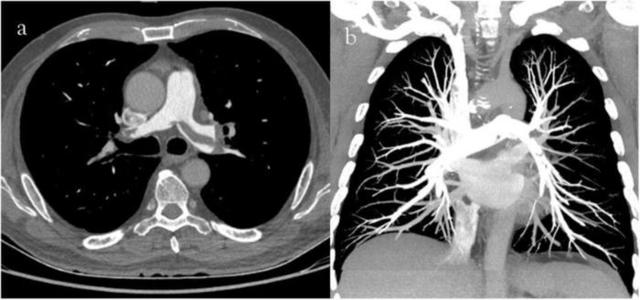

Eski cihazlarda kesit kalınlıkları 1cm civarında iken yeni nesil cihazlar ile 1 mm’nin altına inmiştir. Bu nedenle milimetrik boyuta bile ulaşmayan kitlelerin tanısı mümkün hale gelmiştir. Ayrıca bu cihazların hem görüntü kalitelerinin artmış hem de çekim sürelerinin azalmış olması nedeniyle damar yapılarının incelenmesine olanak sağlar hale gelmiştir. Günümüzde kalp, beyin, boyun, göğüs, karın ve bacakların damarları BT Anjiografi ile rahatlıkla değerlendirilebilmektedir. Konvansiyonel katater Anjiografi yerine daha az yan etkisi olan ve hasta için daha konforlu olan BT Anjiografi işlemleri sıklıkla tercih edilmektedir.

Yeni nesil BT cihazları tek düzlemde değil 3 düzlemde görüntüleme yapabilmekte ve bu sayede 3 boyutlu görüntüler oluşturabilmektedir. Özellikle nakil hastalarında ve akciğer cerrahisi geçirecek hastalarda organ volumlerini hesaplamak için kullanılabilir. Dinamik incelemeler yeni teknolojileri ile daha kolay yapılabilir hale gelmiştir. Bu incelemelerle örneğin karaciğer kitlesi olan bir hastada dinamik görüntüler elde edilerek var olan kitlenin ayırıcı tanısı yapılmaya çalışılır. Travma hastalarında rutin incelemelerden biri haline gelen BT kemik kırıklarını ve kanmaları göstermekte oldukça başarılıdır. BT incelemeleri iyonizan radyasyona yol açtığı için tercih edilirken dikkat edilmeli ve doz hesabı yapılmalıdır.